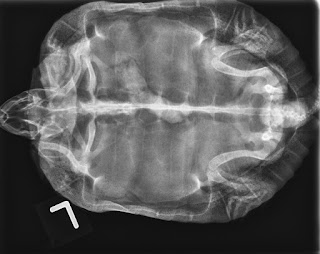

DIAGNOSIS - X-RAYS